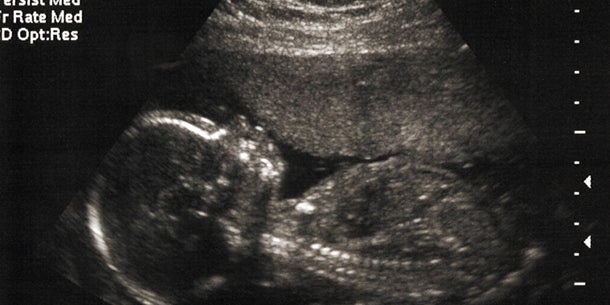

Abtreibung im 5. Monat

Lana war Single, als sie schwanger wurde. Den Vater des Kindes, offensichtlich eine Affäre, bezeichnet sie als "Samenspender". "Als mein Bauch zu wachsen begann, war mein Kopf voller Pläne, wie ich meiner Tochter von Anfang an feministische Ideale beibringen kann", schreibt sie. Als der behandelnde Arzt ihr im fünften Schwangerschaftsmonat mitteilt, dass der Fötus männlichen Geschlechtes ist, bricht für Lana eine Welt zusammen - sie fühlt sich "von ihrem Körper betrogen". Wenige Tage später treibt sie das Baby ab und teilt nun über das Internet ihre Geschichte – sie selber bezeichnet diese als einen Fluch, der sie heimsuchte.